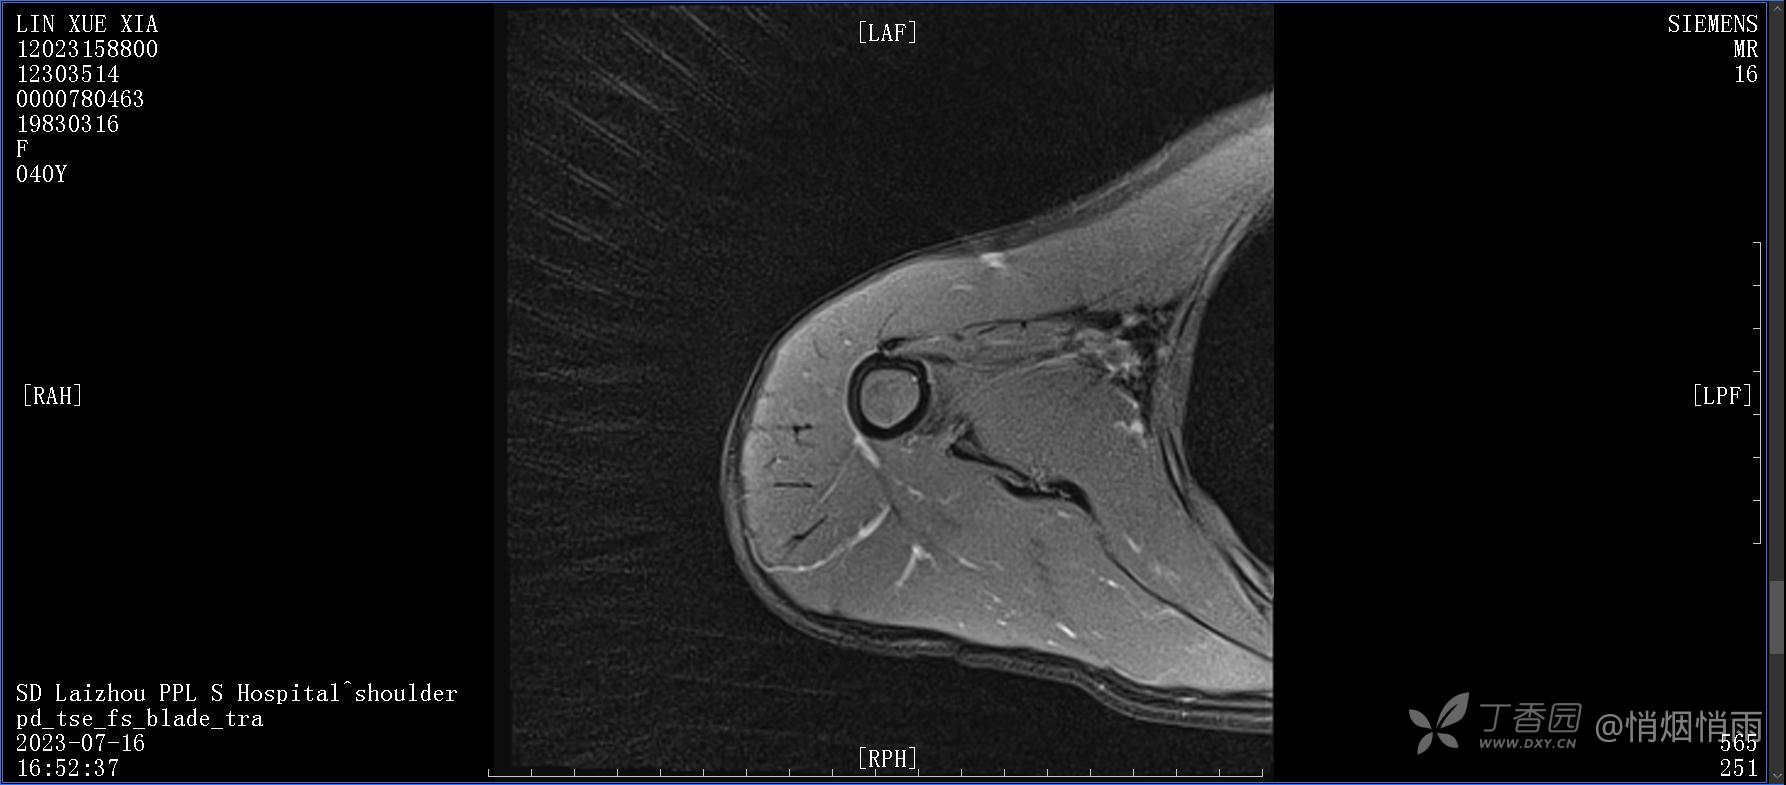

查体:右肩关节局部轻度肿胀,肩胛区压痛明显,痛处不固定,肩关节痛性活动受限,jobe test(+),lift -off test(+),中指、环指感觉较余指减退,余肢端感觉及血运情况可。

目前的诊断,暂时依据辅助检查诊为肩袖损伤,但是患者疼痛的性质和特点,却不是单纯的肩袖损伤所致。考虑过胸廓出口综合征,但是该疾病会出现肩胛区的疼痛吗?(由于考虑到费用的问题,没再进行下一步的检查)带状疱疹会有如此的症状吗?